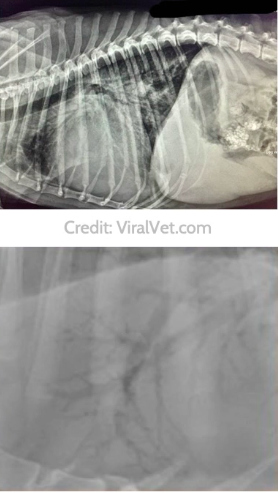

i. Classically see a bronchial pattern

ii. Characteristic “train tracks” and “doughnuts” which are thickened bronchial walls